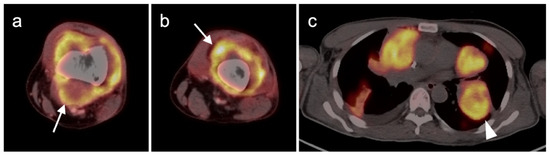

- Uslu, L.; Asa, S.; Sager, S.; Halaç, M. Multiple cardiac masses and distant metastatic foci in a patient with high grade pleomorphic sarcoma of the heart revealed by follow-up FDG PET/CT. Nukl.-Nucl. 2014, 53, N8–N9. [Google Scholar] [CrossRef]